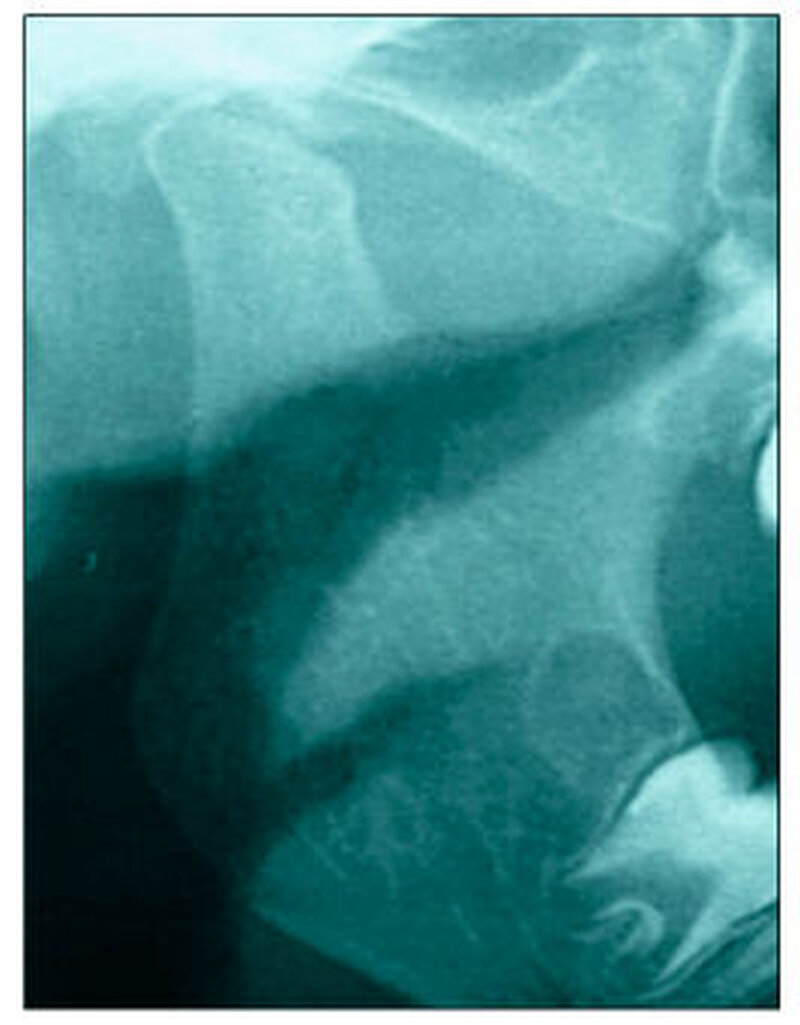

Bereits 2004 wies Carla Evans [Evans, 2005] auf das Risikomanagement bei Allgemeinerkrankungen hin und stellte am Beispiel der JIA dar, dass Unterkieferrücklagen und frontal offene Bisse aus der Kiefergelenkzerstörung entstehen können. Die Röntgenaufnahmen einer JIA-Patientin mit oligoartikulärer Form und Beteiligung des rechten Kiefergelenkes zeigen den typischen Verlauf sehr gut. Bei ursprünglich sehr dezenten Befunden, wie einer s-förmigen Mundöffnung von 44 mm, einer geringen Mittenabweichung um 2 mm nach rechts und einem frontal offenem Biss klagte sie über Schmerzen beim Essen, was den Anlass zur weiteren Diagnostik bot. Die erste Panoramaröntgenschichtaufnahme (Abbildung 1a-c) zeigt auf der rechten Seite einen abgeflachten Kondylus und eine bereits verstrichene Fossa condylaris. Ein Jahr später vermittelt das Fernröntgenseitenbild (Abbildung 1d) trotz fortschreitender kondylärer Resorption ein harmonisches Bild, während nach drei Jahren bei voranschreitendem Abbau des rechten Kondylus (Abbildung 1e) eine Rücklage der Mandibula und eine Bissöffnung manifest sind (Abbildung 1f).